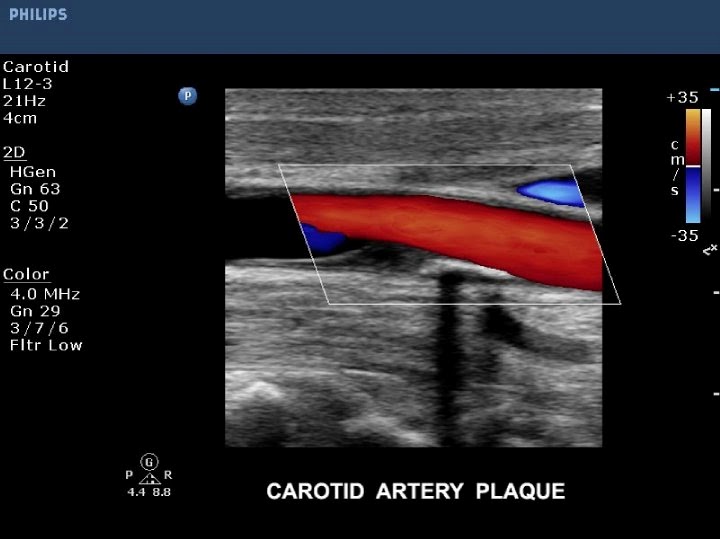

Sertleşme sorununun erektil disfonksiyon en sık sebebi olan penis atar damar yetersizliğinin varlığını ve derecesini belirlemeye yarayan bir ultrasonik görüntüleme yöntemidir.

Bu doppler ölçümlerinde rezistans artışı saptandığında daha yakın takip önerilmektedir. Ankara şehrinde penil doppler ultrasonografi penis damar filmi alanında uzman 34 doktoru inceleyerek ve hasta yorumlarını okuyarak randevu alabilir doktorla iletişime geçebilirsiniz. Peniste ereksiyon halinde iken eğrilmelere yol açabilen peyroni hastalığı bunlardan biridir. İstanbul şehrinde penil doppler ultrasonografi penis damar filmi alanında uzman 26 doktoru inceleyerek ve hasta yorumlarını okuyarak randevu alabilir doktorla iletişime geçebilirsiniz.